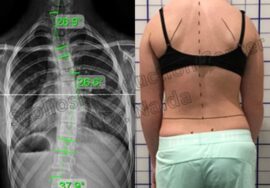

يعتمد التشخيص على عدة خطوات، منها:

الفحص السريري: لتقييم شكل العمود الفقري وطبيعة الحركة.

الأشعة السينية: لقياس زاوية الانحناء ومعرفة مدى التأثير على الفقرات.